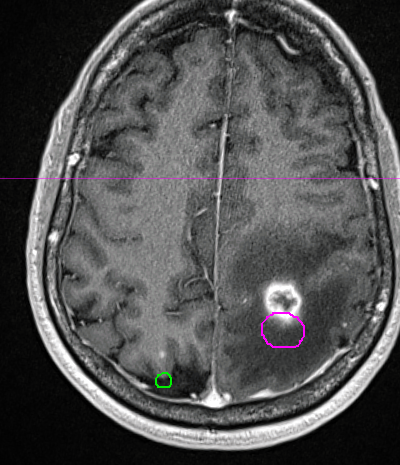

Good illustration of the importance of contrasted sim for these. I see a lot of noncon and MRI fusion. Given the cystic nature of the bigger one, could resim sans contrast prior to treatment and see if the holes match up.pt presented with arm weakness. MRI showed several brain mets and patient was put on steroids. Planning CT w/contrast 2 days after steroid admission showed lesions had shifted due to improvement in edema.

View attachment 369549

View attachment 369550

View attachment 369548

The issue here is not the time between mri and sim, but the steroids changing everything. This is a mim fusion, so nothing to do with postioning due to crappy fusion.